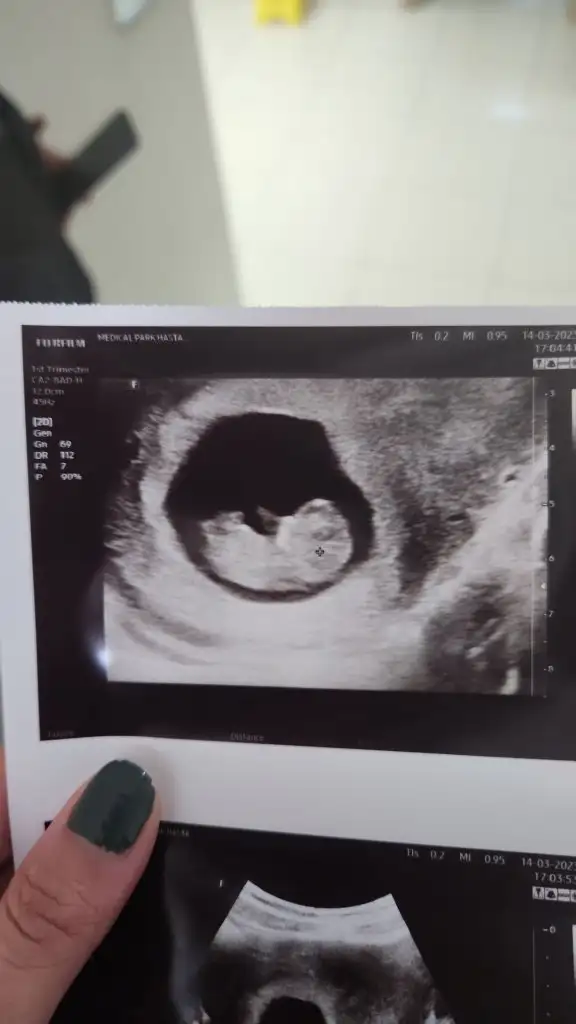

Bana da bir cinsiyet tahmininde bulunur musun 🙈 ilk fotoğraf 6+2 2. Fotoğraf 9+3

• IMG-20230314-WA0001.webp

IMG-20230314-WA0001.webp

16,7 KB · Görüntüleme: 58